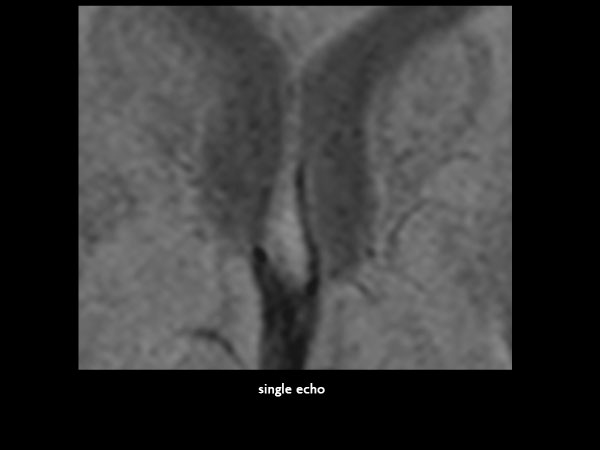

Axial 2D T2* FFE